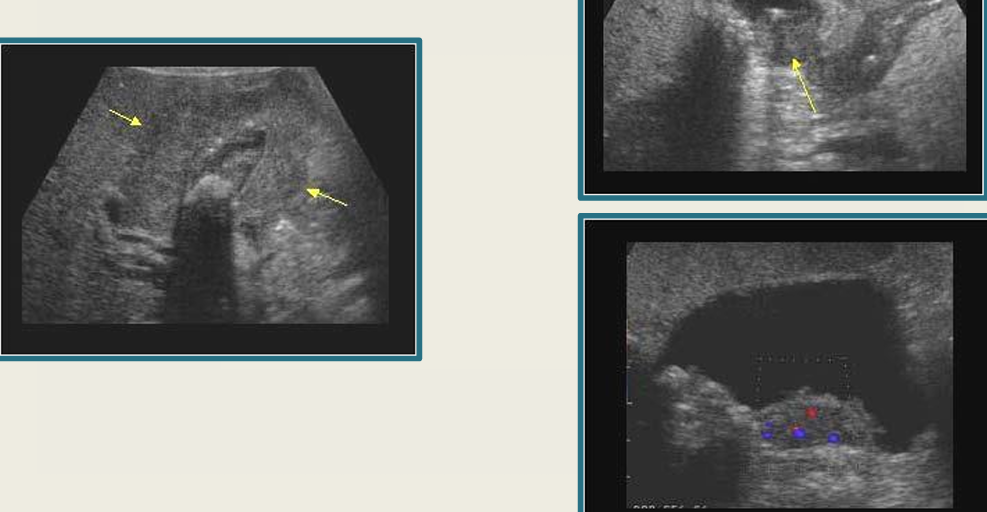

13

New cards

term image

GB carcinoma

14

milk of calcium

15

GB polyps

16

chronic cholecystitis

17

Mirizzi syndrome